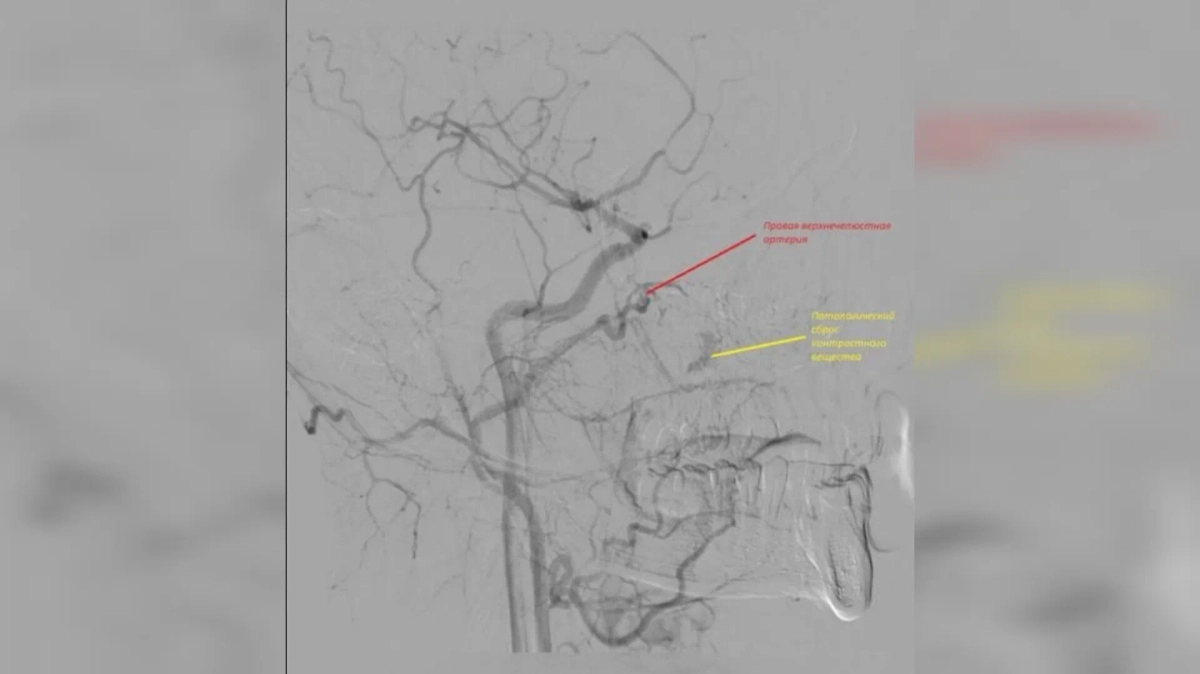

Патологический сброс контрастного вещества (жёлтый). Фото © VK / Орловская областная клиническая больница

Сегмент правой верхнечелюстной артерии. Фото © VK / Орловская областная клиническая больница

Врачи попытались остановить кровотечение с помощью носового тампона, однако поток крови лишь усиливался. В итоге медики прибегли к хирургическому вмешательству. Источник кровотечения они нашли в дистальных отделах правой верхнечелюстной артерии. После операции пациента выписали домой, больше его ничего не беспокоит.